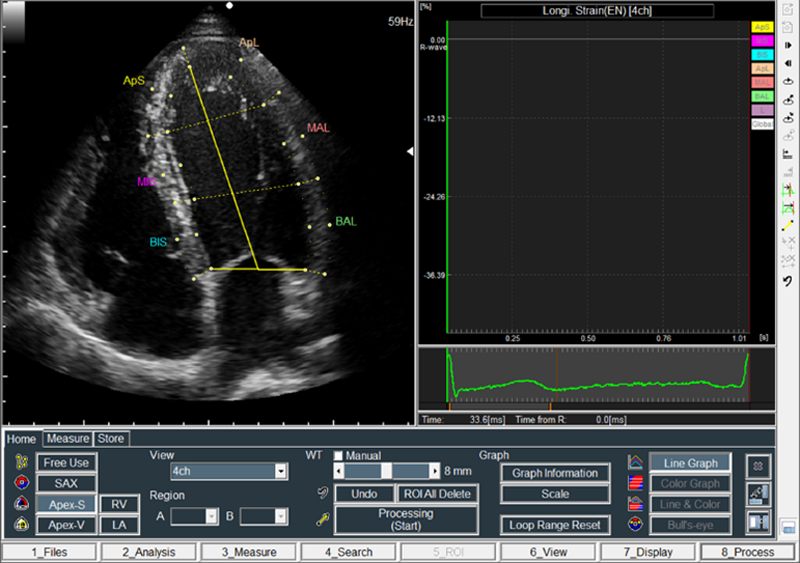

図4に示すように、断面種類の認識とトレースそれぞれの手順を、AI技術を活用した自動化機能によって置き換える。最初に、動画像に対して、断面種類の学習済データを参照しながら断面種類の認識を行う。次に、断面種類に応じたトレース線の学習済データを参照しながらオートトレースを行う。最後に、トレース線に対してトラッキングを行い、計測値を算出する。これらの一連の処理を自動で行う。図5は、画像読込後にオートトレースまで処理した結果の画面である。画像読込後、およそ4秒程度で、1断面1心拍分の計測結果を表示できる。一方、手動計測や修正操作を必要とする場合にも配慮し、断面認識、オートトレースの自動と手動の切り替えも可能になっている。

図5 断面認識とオートトレース処理後の画面(View欄に4chと、トレース線が自動設定される)